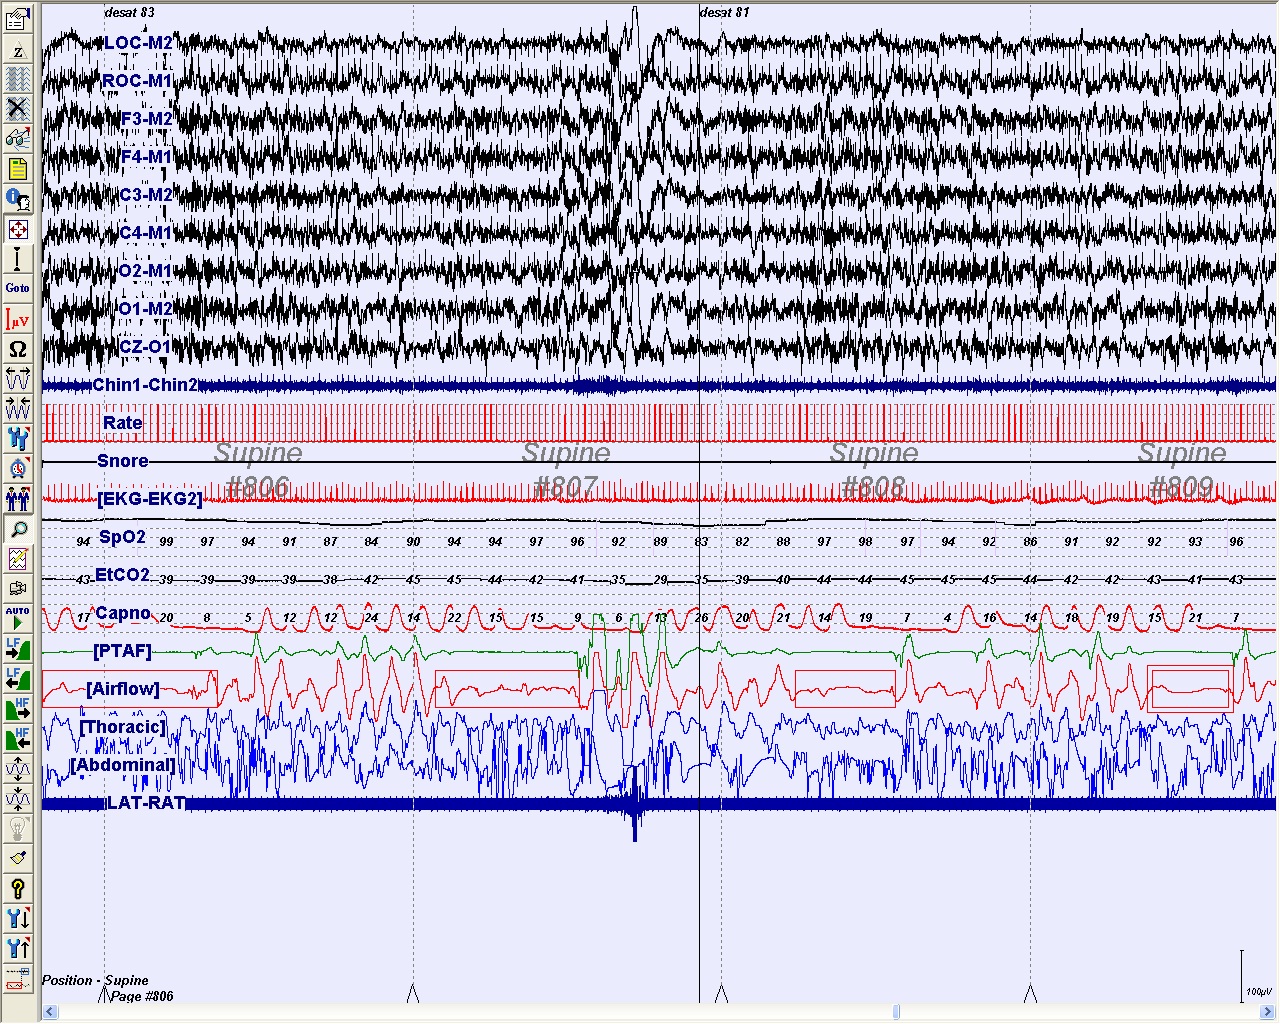

The patient had an elevated apnea-hypopnea index (AHI) of 21.5 events/hr of sleep with the lowest measured oxygen saturation at 68% (see panel A). He was subsequently referred to otolaryngology for adenotonsillectomy (AT) due to tonsillar hypertrophy. After surgical treatment, his daytime sleep was less prevalent, his snoring improved but did not completely resolve, and the nighttime arousals were less frequent.

Panel B demonstrates a 2-minute epoch from a repeat nocturnal PSG that was performed 3 months after surgery. The AHI was persistently elevated at 12.6 events/hr of sleep with lowest measured oxygen saturation of 80%.